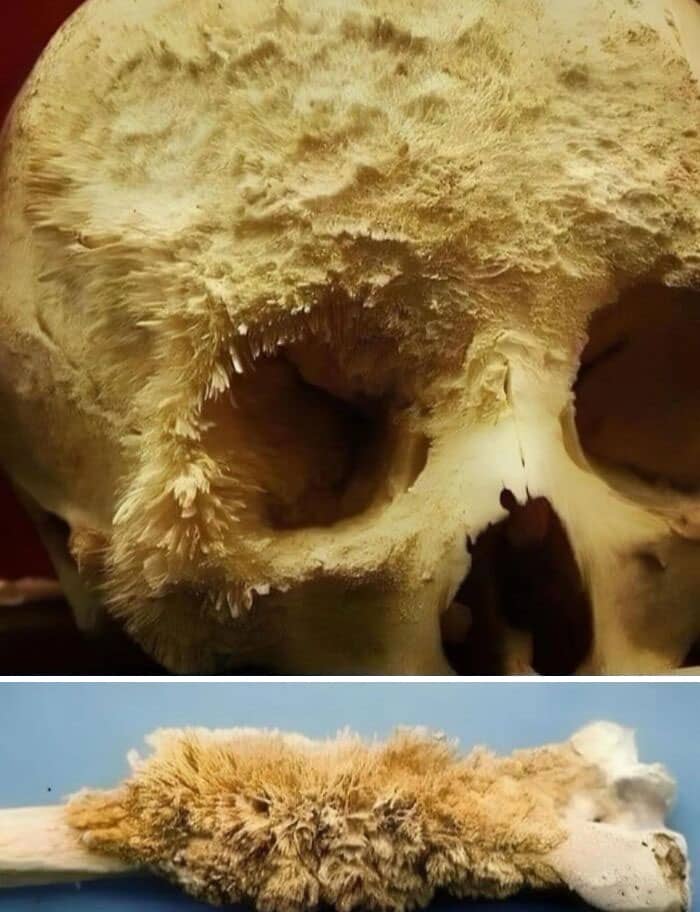

#26 Human Skull With Stage 1 Bone Cancer. Credit : Prinoth-1